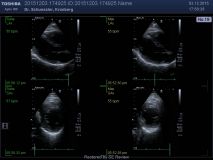

Ultraschalluntersuchung des Herzens mit Belastung (Streßechokardiographie)

Die Streßechokardiographie wird vorwiegend bei Verdacht auf - oder zum Ausschluss einer koronaren Herzerkrankung eingesetzt. Sie erlaubt einen direkten Vergleich der Bewegung des Herzens in Ruhe und unter körperlicher Belastung. Hierzu werden zunächst in Ruhe, mittels Echokardiographie, Aufnahmen der Herzbewegung erstellt. Gleiches erfolgt nach Erreichen der maximalen Last auf dem Ergometer. Sofern es unter Belastung zu einer Minderdurchblutung des Herzmuskels kommt, lässt sich dies in der vergleichenden Betrachtung der Aufzeichnungen durch das Auftreten einer Bewegungsstörung des Herzmuskels erkennen.

Die Auswertung der Untersuchung erfolgt mittels computergestützter Analyse der Bewegung und Funktion der einzelnen Segmente des Herzmuskels